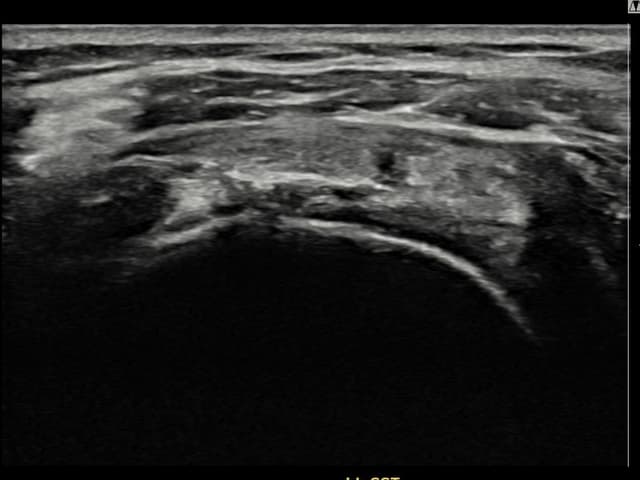

[촬영시기:22.09.28]

[석회분쇄흡입술] 우측 어깨 통증으로 밤잠을 못 이루고 팔을 올리기 어려워진 30대 여성 환자로, X-ray에서 우측 극상근건 내 석회 침착이 확인되어 석회분쇄흡입술을 시행하였습니다.